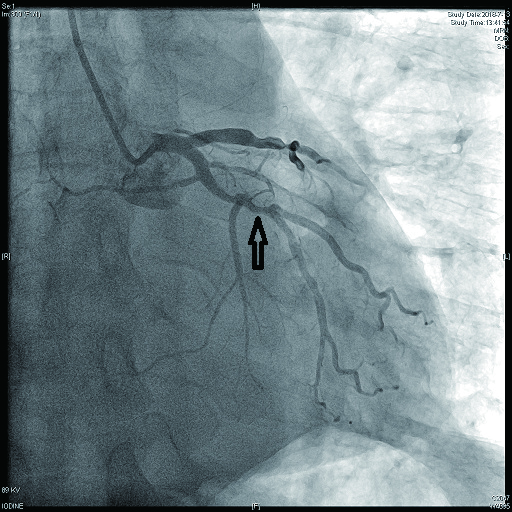

2 结果 本研究收集7例De winter综合征患者,6例进行了急诊冠脉造影,胸痛至球囊扩张平均时间为3.3 h,1例进行择期冠脉造影。其中,3例为前降支近段严重病变,1例为第一对角支闭塞,3例为前降支中段闭塞,2例合并多支血管病变,5例为单支血管病变,均行前降支支架植入术(表 4)。1周内行心脏彩超检查,4例出现室壁运动减弱,2例EF值小于50%,2例心脏形态结构未见异常,1例患者术后第2天因个人原因自动出院,未完善心脏彩超(表 5)。观察7例患者住院期间心电图演变情况,其中有3例在PCI术后出现前壁导联ST段抬高,4例未出现ST段抬高(表 5)。病例1住院期间出现室性心动过速,病例7患在急诊科就诊时发生呼吸心搏骤停,经抢救后送导管室行急诊冠脉造影。另外,所有患者经药物及介入治疗后,均症状缓解出院,院外长期服用阿司匹林100 mg/d+替格瑞洛90 mg/12 h+阿托伐他汀40 mg/瑞舒伐他汀20 mg等药物,出院1个月后电话随访,7例患者均无胸痛、气促发作及再住院,无死亡病例。

表 4 7例患者冠脉造影及介入治疗情况

| 编号 |

是否急诊冠脉造影 |

冠脉造影结果 |

介入治疗情况 |

| 病变血管支数 |

罪犯血管 |

罪犯血管狭窄程度 |

罪犯血管TIMI血流 |

| 病例1 |

是 |

1 |

LAD近段(图 9) |

75%~90% |

2级 |

LAD近段植入支架1枚 |

| 病例2 |

是 |

3(图 6~8) |

LAD近段 |

次全闭塞 |

2级 |

LAD近段植入支架1枚 |

| 注:LAD为左冠状动脉前降支; TIMI为心肌梗死溶栓治疗 |

表 5 7例患者的心电图演变及心脏彩超结果

| 编号 |

心电图是否演变为ST段抬高 |

心脏彩超 |

| 病例1 |

是(图 3~5) |

左心扩大,左室前间壁、前侧壁及心尖部运动减弱,EF 35% |

否(图 1~2) |

心脏形态结构未见异常,EF 56% |